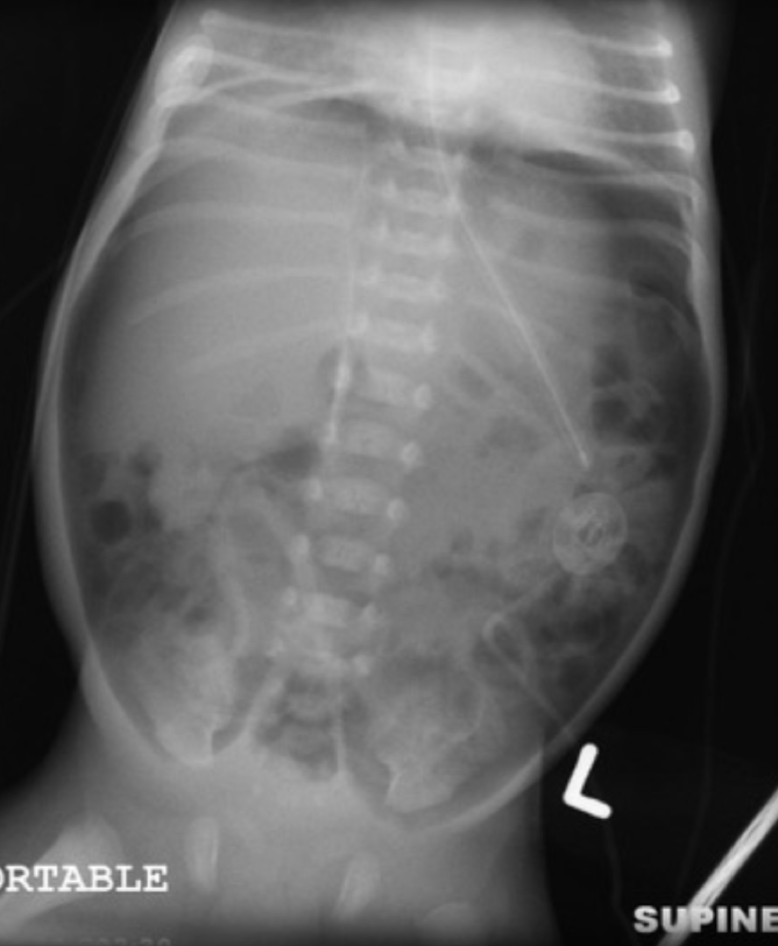

What is this?

What is pneumatosis intestinalis